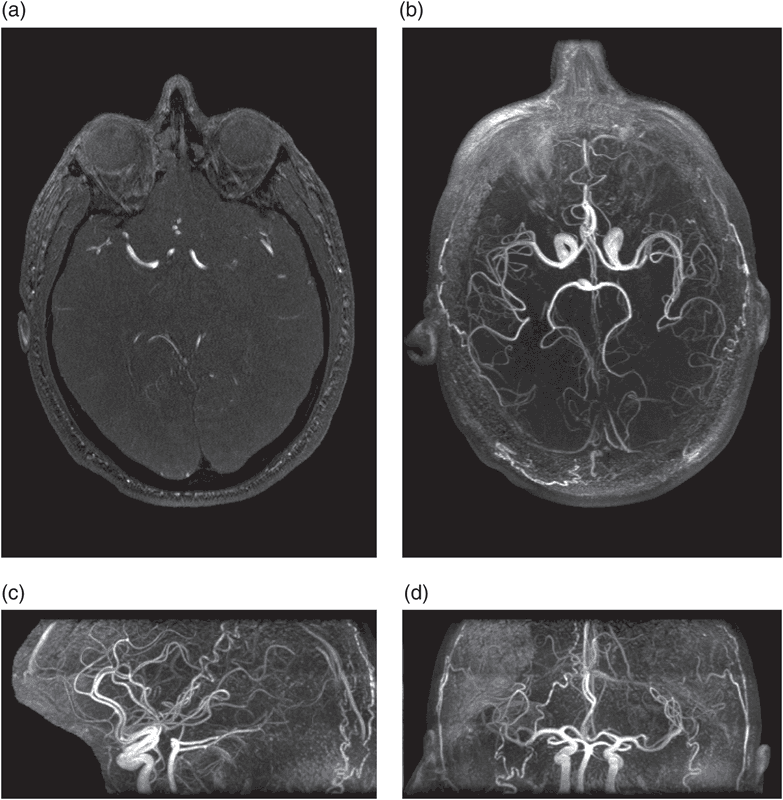

- Chụp lại chuỗi xung của tĩnh mạch theo như bộ thu tín hiệu của vùng mạch ngoại biên.

- Tái tạo lại bình diện (viết tắt là MPR) và hệ không gian ba chiều (VRT).

- Hình ảnh hiện thị sắc nét với những cấu trúc giải phẫu cụ thể trong vùng được thăm khám.